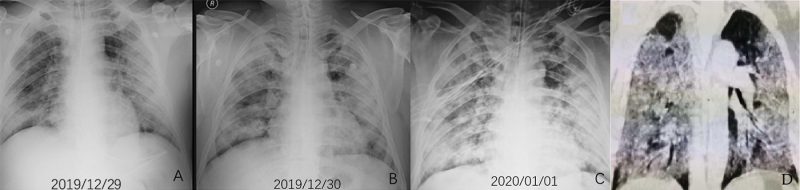

– Pan và cộng sự [6] quan sát ở 21 bệnh nhân được xếp loại thể nhẹ (không có suy hô hấp, không thở máy) thì diễn tiến của bệnh được chia thành 4 giai đoạn tương ứng với biến đổi của các biểu hiện trên hình CLVT: 1/ giai đoạn sớm (0-4 ngày), trong giai đoạn này thì hình ảnh đám mờ kính đục là chủ yếu, diện thương tổn nhỏ; 2/ giai đoạn tiến triển (5 -8 ngày), trong giai đoạn này, viêm nhiễm trở nên trầm trọng và lan rộng hơn, từ biểu hiện đám mờ kính đục xuất hiện thêm biểu hiện lát đá không đều và đặc phổi; 3/ giai đoạn đỉnh điểm (9 -13 ngày), trong giai đoạn này thì tốc độ lan rộng của thương tổn chậm lại, hình ảnh đặc phổi chiếm ưu thế bên cạnh thương tổn đám mờ kính đục lan tỏa và mẫu hình ảnh lát đá không đều, xuất hiện các dải xơ trong nhu mô; 4/ Giai đoạn hấp thu (trên 14 ngày), trong giai đoạn này thì tình trạng viêm nhiễm được kiểm soát, thương tổn đặc phổi được hấp thu dần qua trung gian hình kính đục đơn thuần và không có hình ảnh lát đá không đều, sau đó thì xóa mất hoặc xuất hiện các dải xơ.

– Trong trường hợp diễn tiến xấu đi về mặt lâm sàng thì trên hình ảnh CLVT cho thấy các biểu hiện biến đổi theo hướng gia tăng mức độ trầm trọng; nghiã là thương tổn gia tăng về mặt số lượng, phân bố lan tỏa hơn, số thùy phổi bị tác động nhiều hơn [7,1011,12]; thương tổn gia tăng kích thước, lúc này vị trí thương tổn không chỉ khu trú ở ngoại vi dưới màng phổi mà còn lan dần về phía trung tâm; về mặt đậm độ thì thương tổn các loại có biểu hiện gia tăng đậm độ hơn, với loại thương tổn dạng kính đục thì tăng dần mật độ theo hướng hình thành đám mờ kiểu lát đá không đều (do dày ra của vách liên tiểu thùy và xuất hiện các vách bên trong tiểu thùy phổi) và mô phổi đặc thay thế dần diện kính đục, với loại thương tổn dạng đặc phổi thì đậm độ cũng gia tăng hơn, tạo nên hình ảnh “phổi trắng”, điều này khiến chức năng của phổi suy giảm hẳn. Một điểm đặc biệt là trong tiến triển của thương tổn của viêm phổi COVID-19 không có sự hình thành hốc hoại tử như trong các bệnh lý viêm phổi do nhiễm trùng. Các tiến triển xấu đi của thương tổn thường gặp ở nhóm bệnh nhân già, có bệnh lý nền (hình 4,5) .